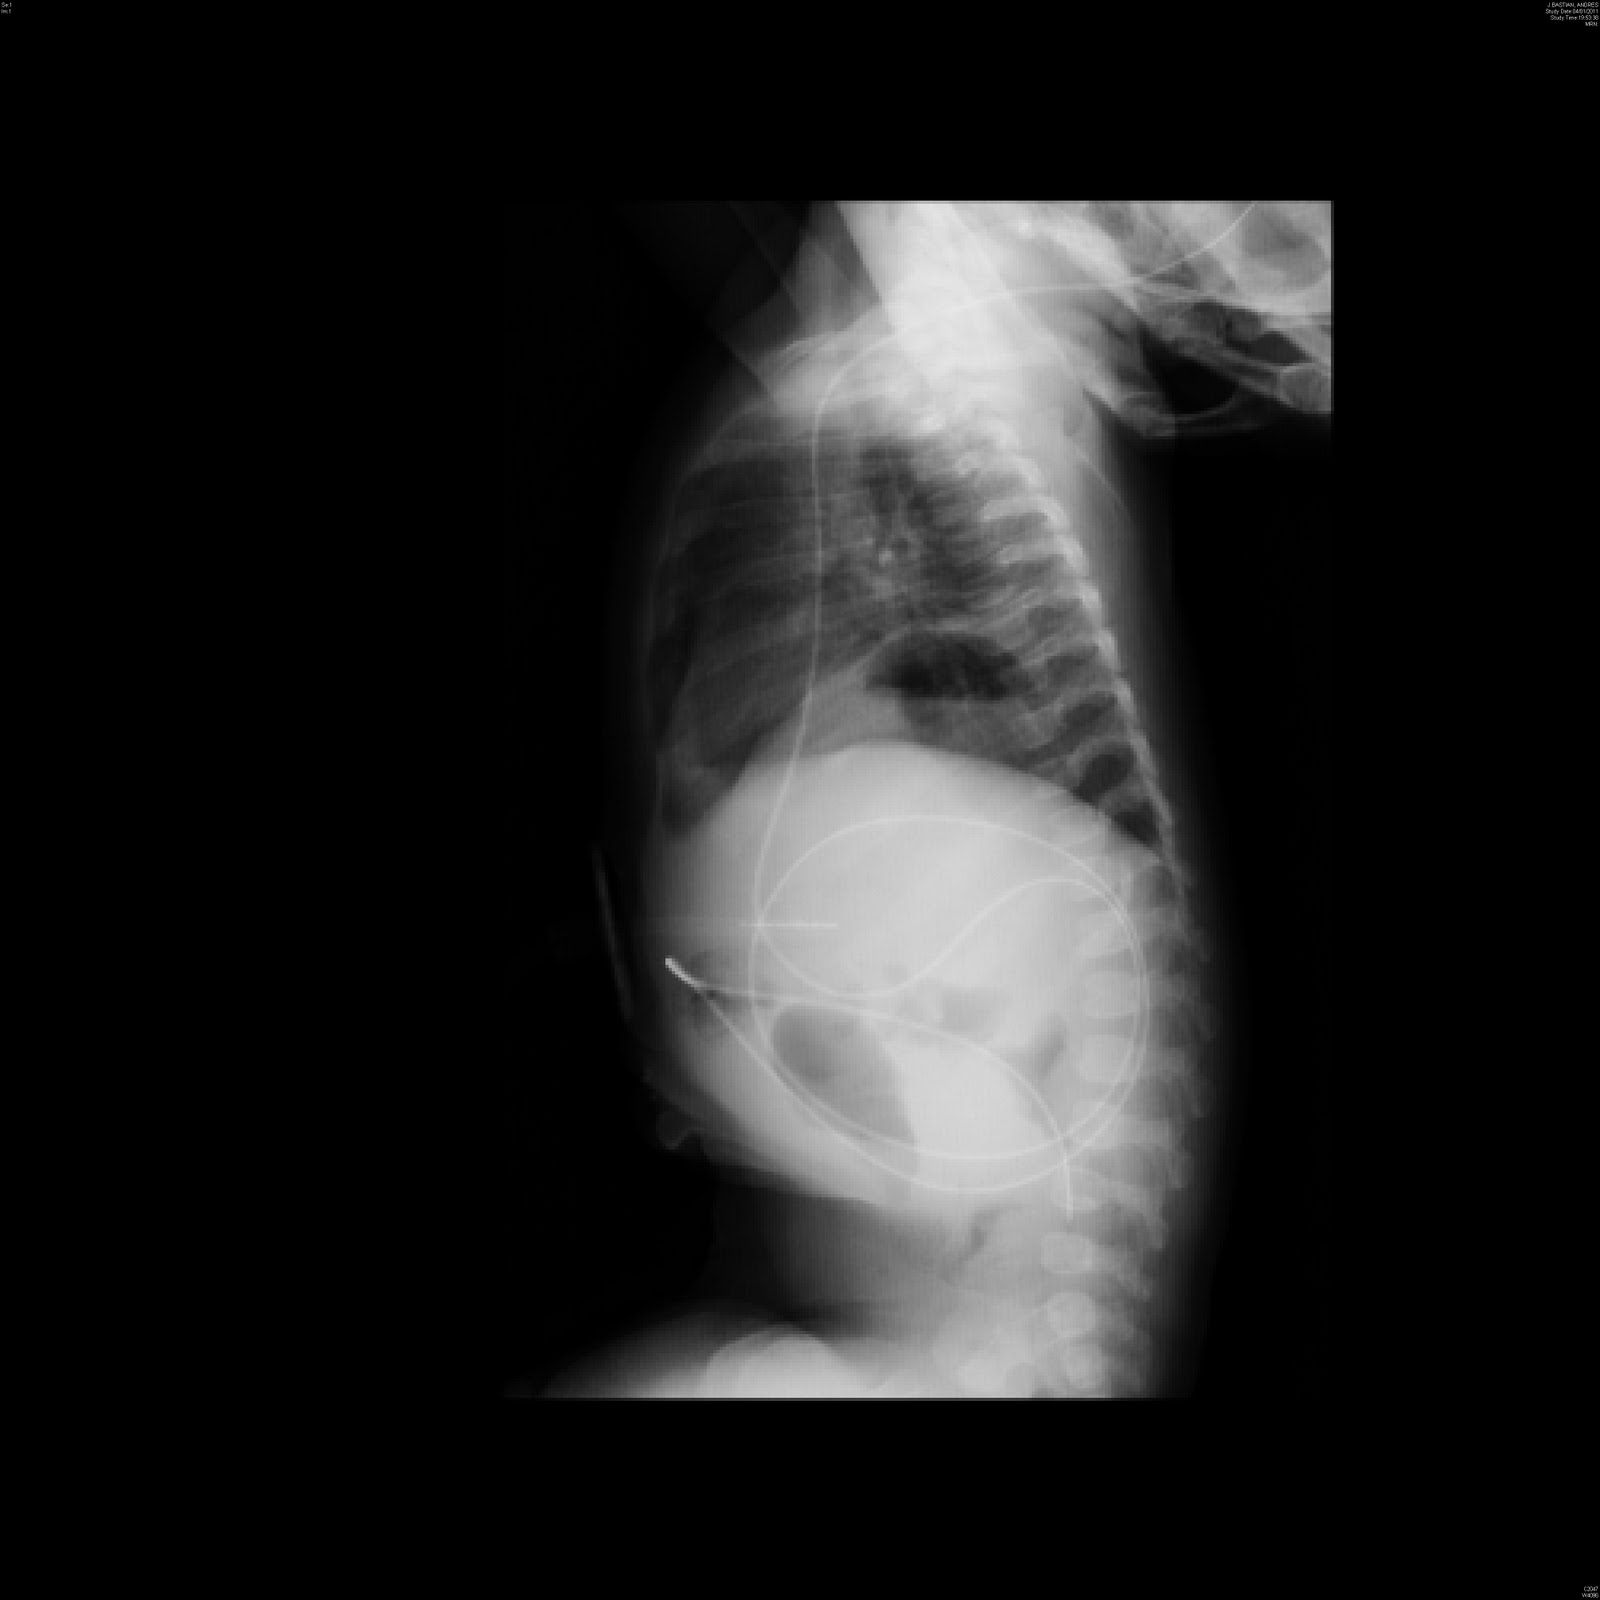

Cuál es su diagnóstico

Paciente de 4 meses con antecedente de operación antirreflujo (Nissen)a los 2 meses de vida, ingresa por un cuadro de vómitos frecuentes de contenido gástrico de 24 hrs. de evolución.